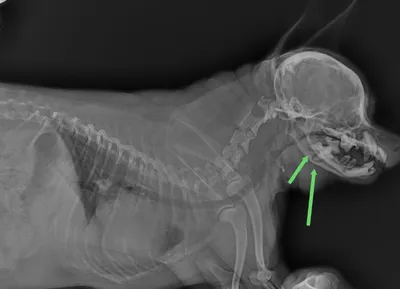

Почему хроническая инфекция растворяет кость и при чём тут почки. Зубной камень, хроническое воспаление, прикорневые абсцессы это: 🐾 постоянный источник бактерий, 🐾 постоянная боль, 🐾 хроническое

13 мар. 2026 г.

5.6k 273 40